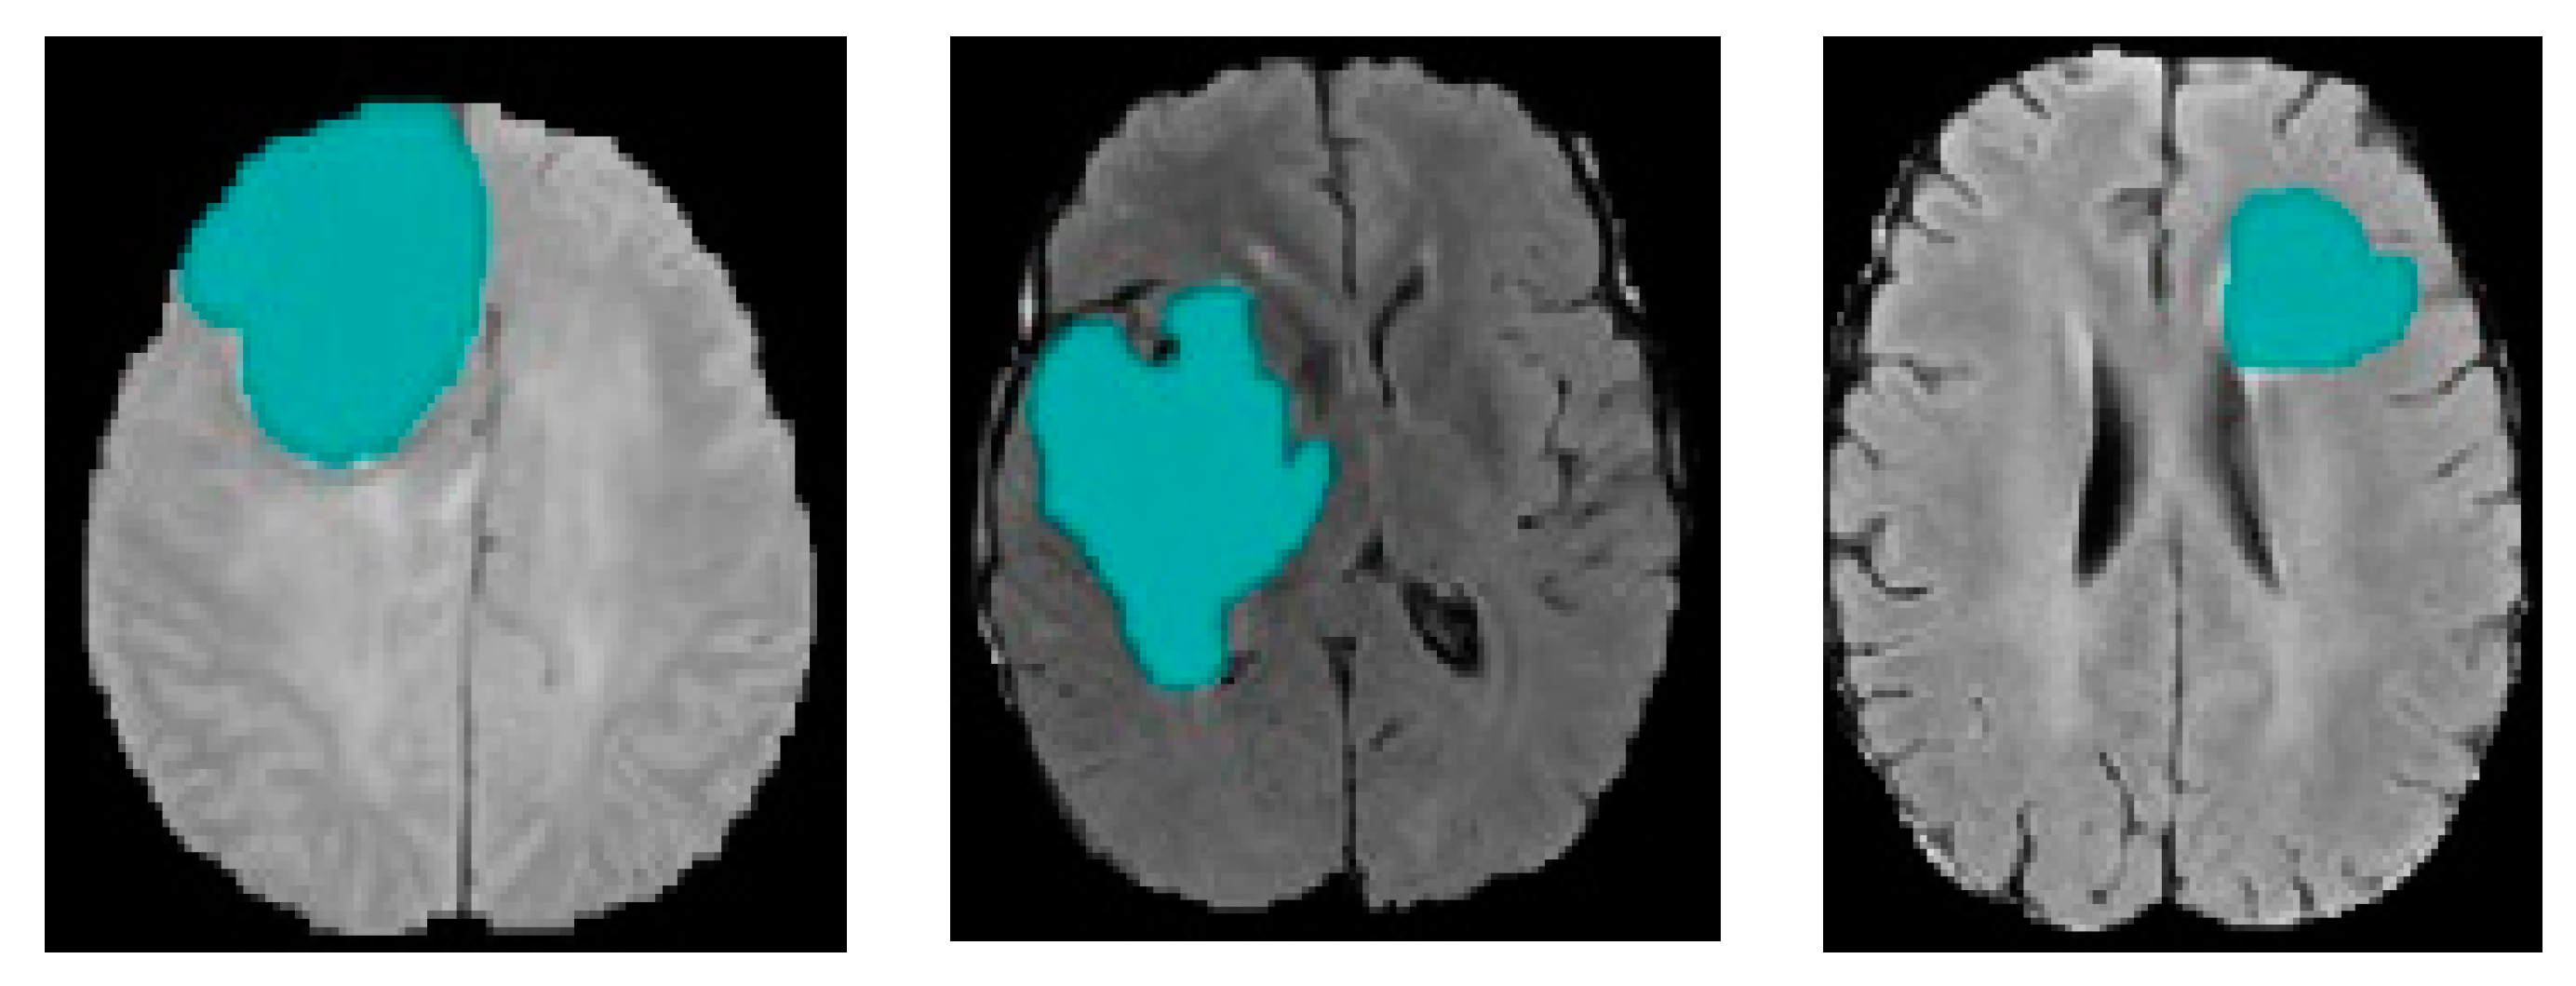

4. Experimental Results